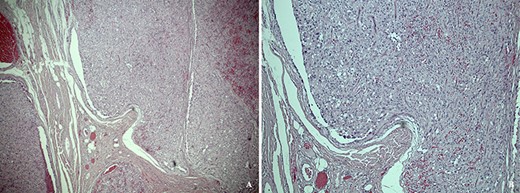

Unexpectedly, histological examination revealed a large, subcutaneous, lobulated tumour with pleomorphic tumour cells (Fig. 1). The tumour cells appeared diffusely and strongly positive for S100, CD56, vimentin, glial fibrillary acidic protein (GFAP) and TFE3. Other epithelial and neuroendocrine immunostains were negative. On sections reviewed, the tumour was found to possibly extend to one of the lateral circumferential resection margins, suggesting incomplete excision. The histology was reviewed by specialist paediatric neuropathologists, who confirmed a diagnosis of subcutaneous ependymoma of myxopapillary subtype (World Health Organisation (WHO) grade 1). The patient subsequently underwent magnetic resonance imaging (MRI) of the neuraxis, which confirmed that the tumour was extraspinal in origin.

(a) Low power hematoxylin and eosin stain showing a subcutaneous tumour composed of lobules of pleomorphic epithelioid cells. (b) High power photomicrograph showing a multi-nodular nested architecture separated by fibrovascular septa, and a perivascular arrangement of cells reminscient of pseudorosettes.